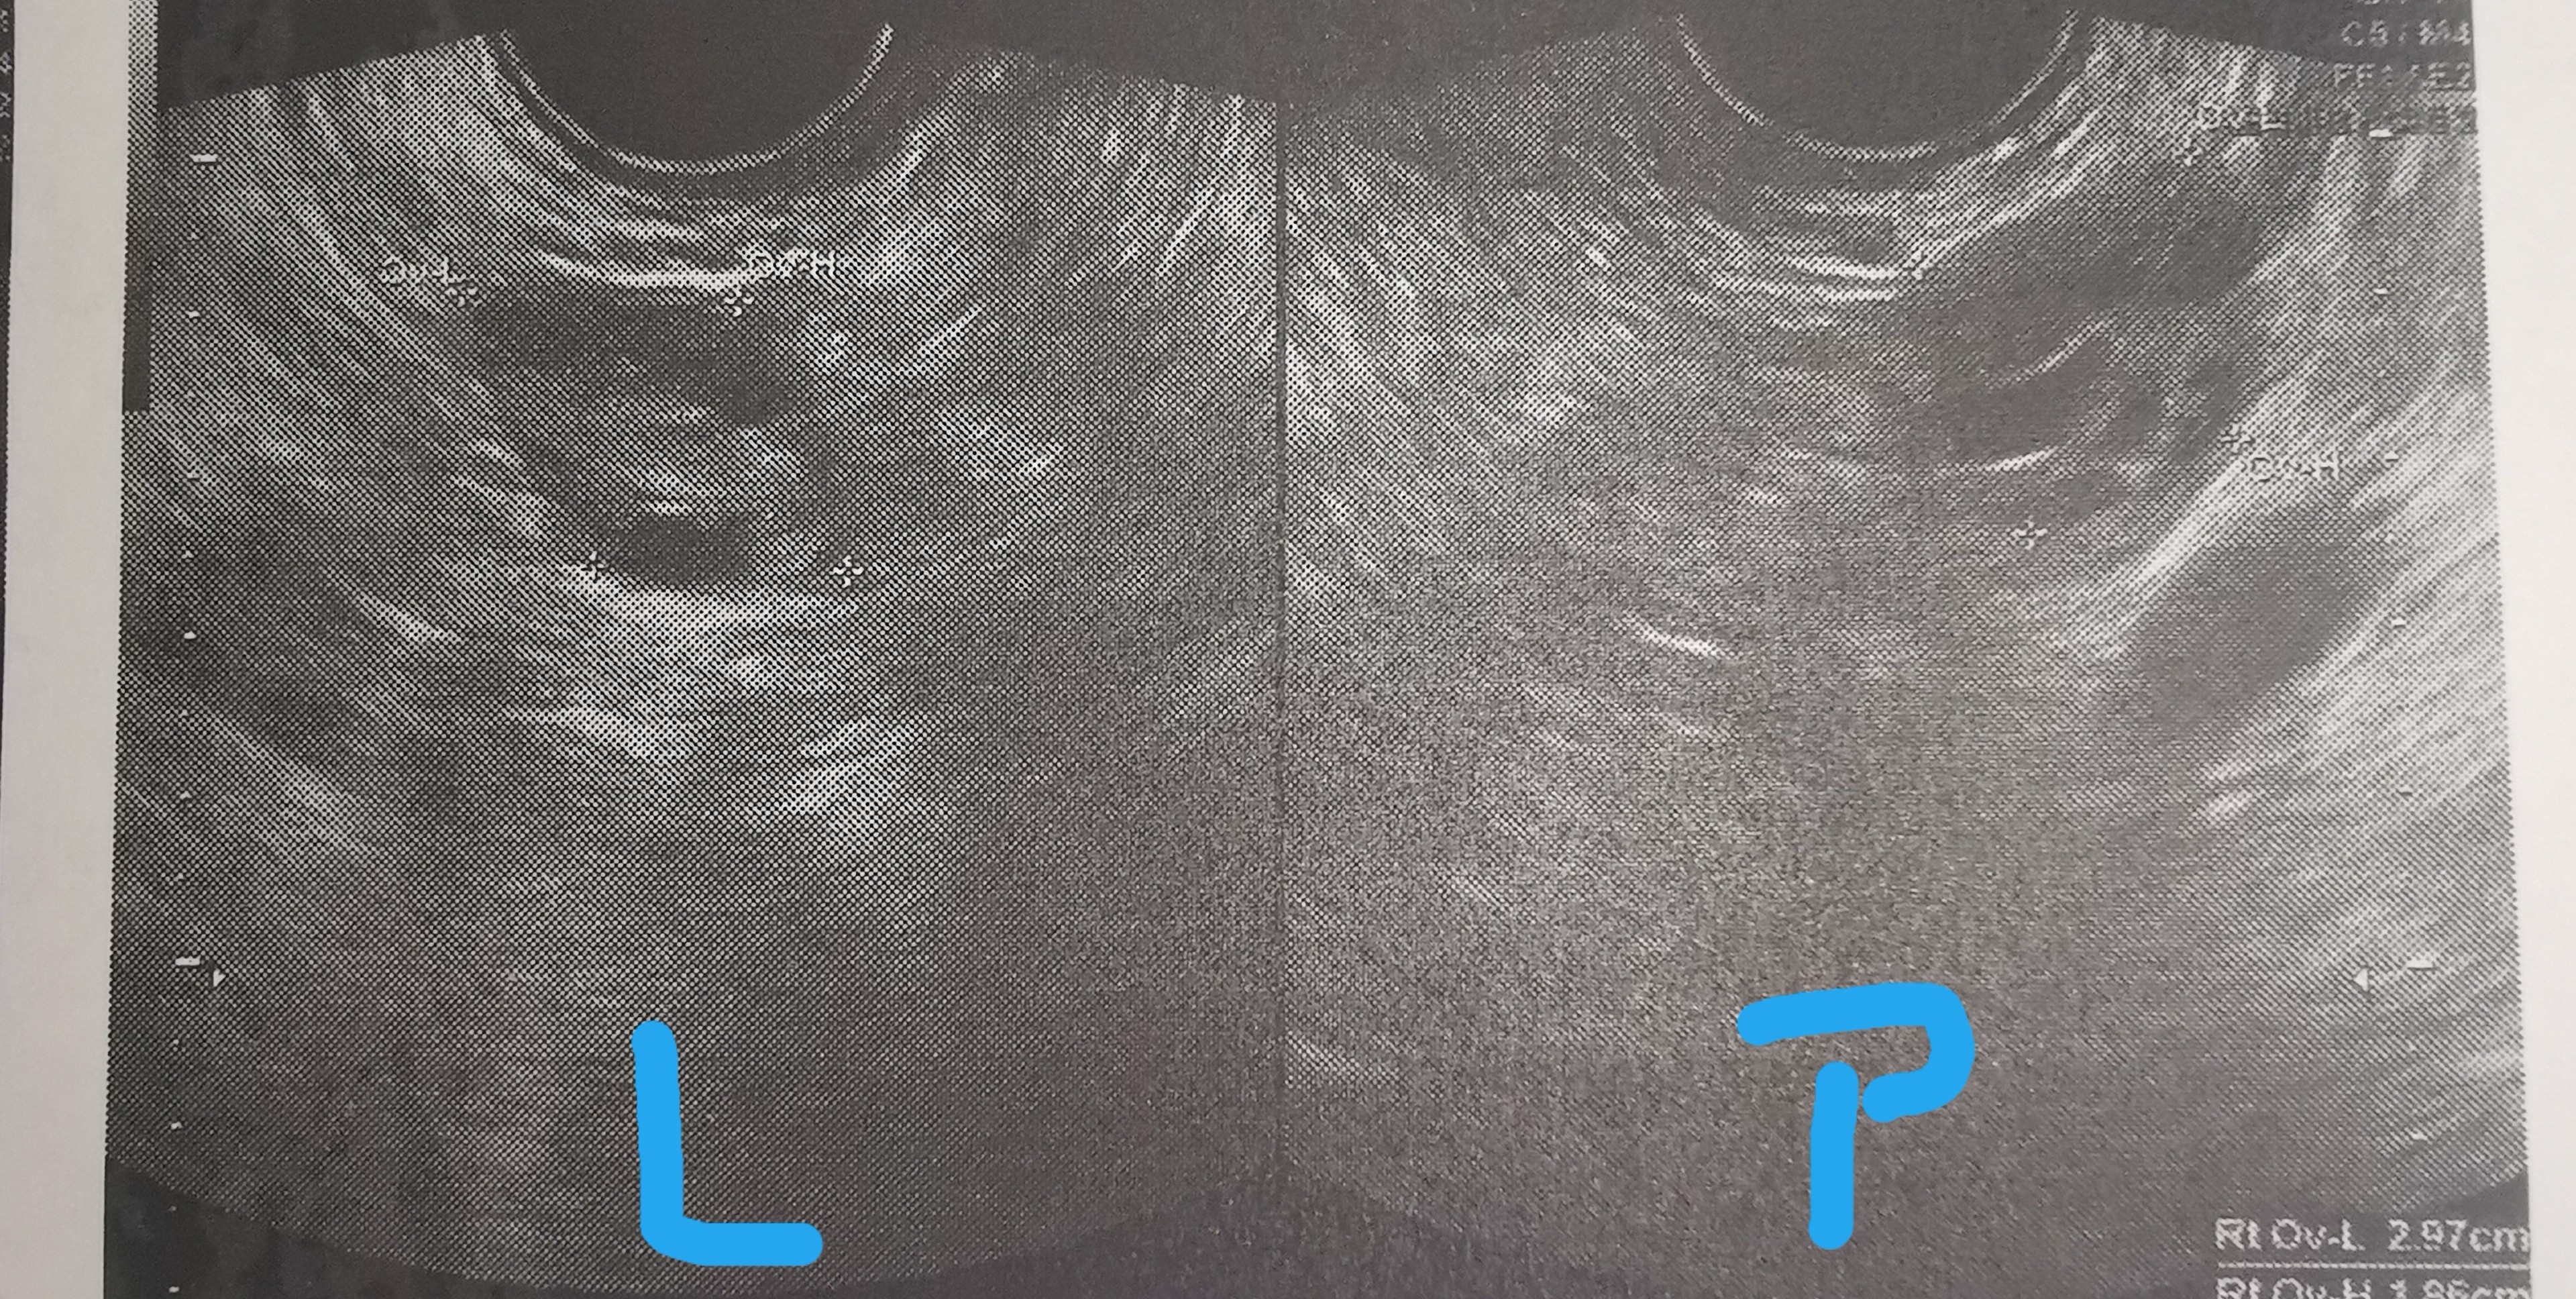

A byłaś u ginekologa? Wiesz jakiej grubości masz endometrium?